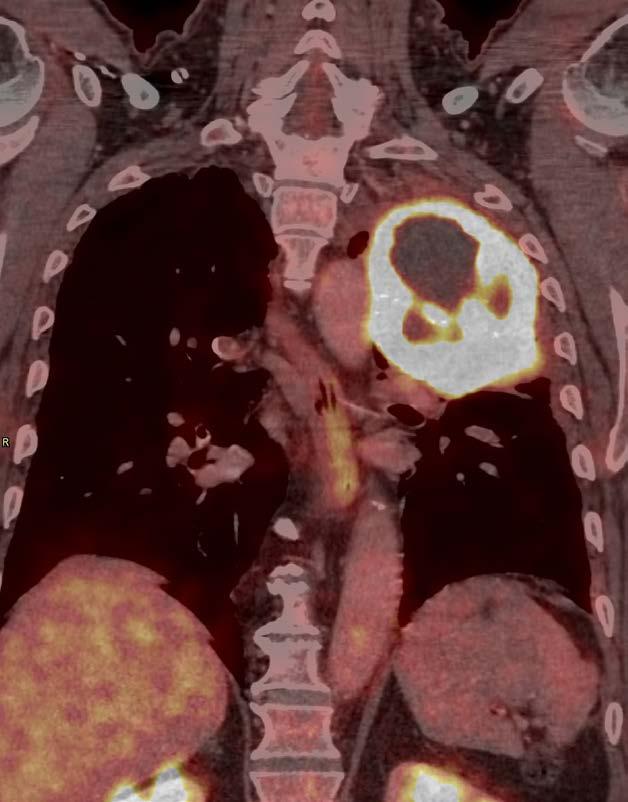

Á síðastliðnum tveimur áratugum hafa orðið miklar framfarir í greiningu lungnakrabbameins, ekki síst með tilkomu jáeindaskanna og berkjuómspeglunar, sem hafa bætt stigun sjúkdómsins og gert meðferð markvissari. Sömuleiðis hafa orðið miklar framfarir í meðferð sjúkdómsins, ekki síst með tilkomu skurðaðgerða þar sem notast er við brjóstholssjá sem stytt hafa legutíma og fækkað fylgikvillum. Sömuleiðis nýtist hnitmiðuð geislameðferð oftar sjúklingum sem ekki er treyst í skurðaðgerð. Mestar hafa framfarirnar þó orðið í meðferð útbreidds lungnakrabbameins, ekki síst með tilkomu öflugra líftækniog ónæmishvetjandi lyfja sem nota má til að klæðskerasauma meðferð út frá mælingum á stökkbreytingum og lífmörkum í æxlunum.